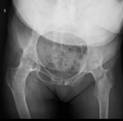

常规开展膝、髋、肩、肘关节置换及翻修手术,并开展单髁置换、胫骨高位截骨术等。治疗各类关节创伤及疾病,如股骨头缺血坏死,膝关节老年性骨性关节炎、类风湿关节炎,股骨颈骨折,股骨转子间骨折。

双侧强直髋术前/术后